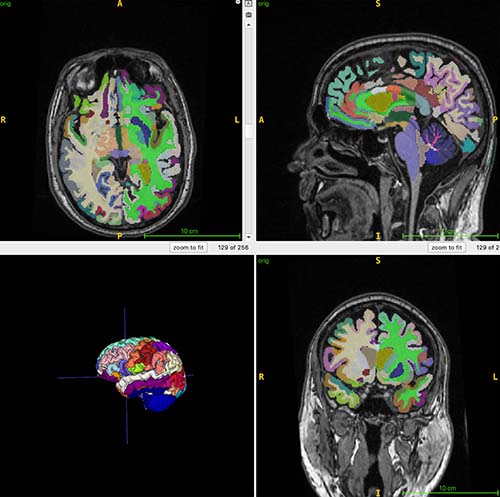

For the ongoing study, 1,164 healthy individuals (52% women) from four sites were examined with whole-body MRI. The mean chronological age of the participants was 55.17 years. The researchers combined MRI imaging with T1-weighted sequences, a technique that produces images where fat appears bright and fluid appears dark. This allows for optimal imaging of muscle, fat and brain tissue. An artificial intelligence (AI) algorithm was used to quantify total normalized muscle volume, visceral fat (hidden belly fat), subcutaneous fat (fat under the skin) and brain age.

Figure 2: This color-coded brain figure shows an example of segmented regional volumes obtained from the 3D T1 volumetric MRI scans used for the artificial intelligence (AI) computations of brain age used in this study.